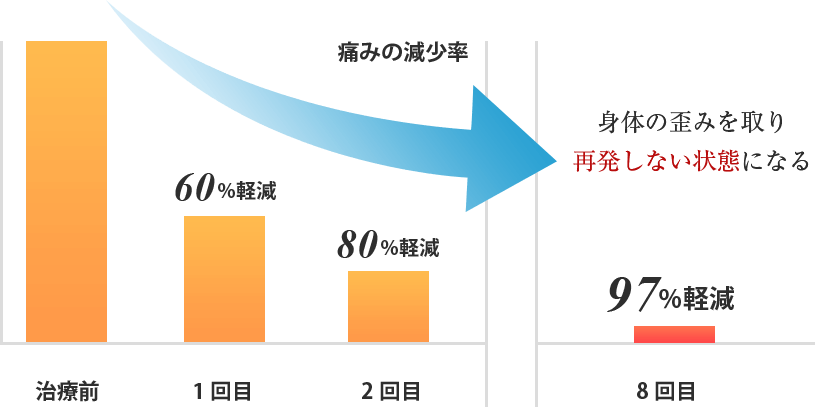

慢性的な膝や腰の痛み、頭痛、肩こり、外反母趾、骨盤の歪み、婦人科系疾患、慢性疲労、不眠、カラダのたるみ、便秘と多様な悩みに苦しむ方をこれまで施術してきましたが、どの方も共通していたのは「距骨」が歪んでいたことでした。 日常的な様々な痛みや症状の原因は、この土台である距骨にあるのです。

距骨を整える事により痛みの無い健康なカラダを取り戻して行きます。